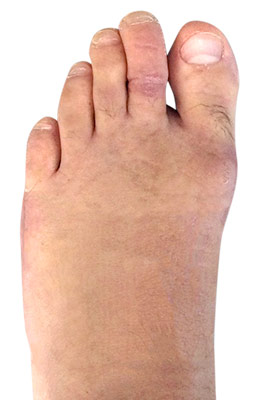

Minimally Invasive Bunion Surgery featuring the CrossRoads miniBunion™ System

Eva is a 24-year-old female who had just began working at a job that required high fashion shoes. She was in constant pain but could not take time off work. Our miniBunion™ Minimally Invasive Bunionectomy allowed her to continue to work and be on her foot with full recovery and return to regular shoes by 6 weeks. She had an amazing range of motion, no more bunion pain, and absolutely no visible incision. After picture taken six weeks post-surgery.